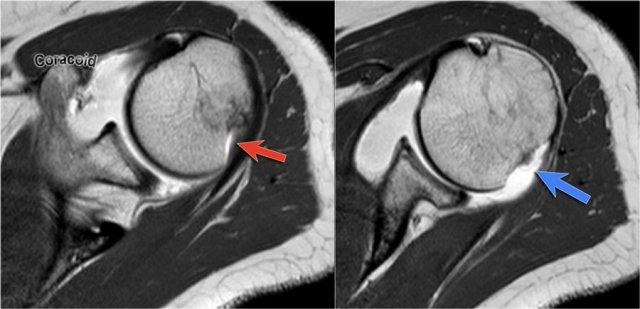

Có hình ảnh bong tách sụn viền trước-dưới (vị trí 3-6 giờ) với rách hoàn toàn màng xương bả vai phía trước.

Mũi tên chỉ vào màng xương bị gián đoạn.

Trên MRI khớp cản từ, sụn viền vắng mặt ở phía trước ổ chảo và mảnh sụn viền bị di lệch ra trước (mũi tên).

Có tổn thương Bankart xương (mũi tên đỏ cong).

Đường rách lan lên trên (mũi tên đen).

Ngoài ra còn có khuyết Hill-Sachs (mũi tên đỏ).

Hình MRI khớp cản từ mặt phẳng đứng dọc cho thấy sự lan rộng lên trên của đường rách Bankart.